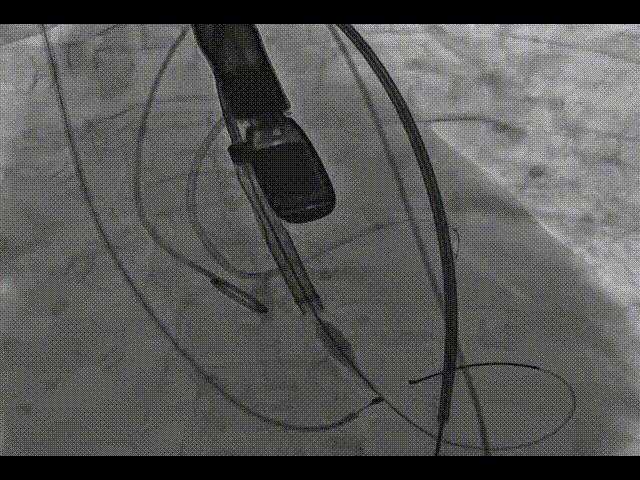

主动脉根部造影

左冠造影及保护

20mm球囊预扩,无漏,冠脉灌注良好

TaurusOne释放过程

瓣膜完全释放

22mm球囊后扩